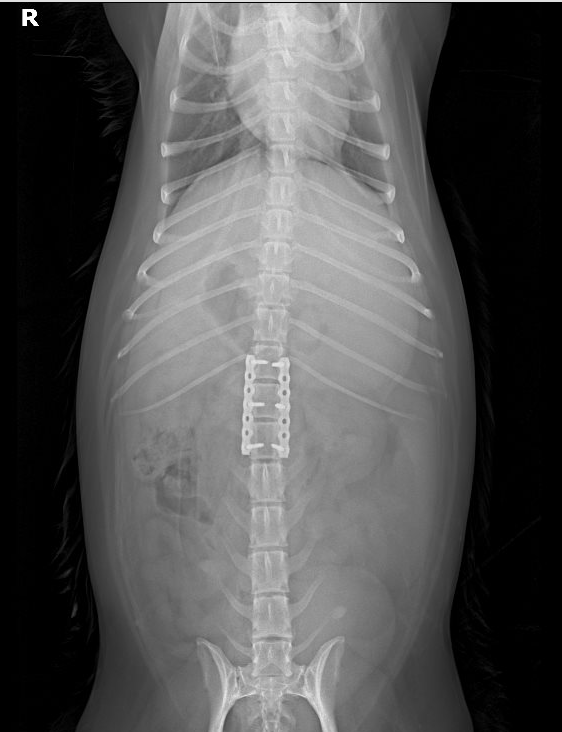

胸腰椎核磁检查

检查部位:胸椎/腰椎MRI平扫检查

检查序列:T1序列,T2序列,压脂序列,压水序列,共218张图⽚⽤于结果判读。

影像所⻅:

1、L1-L2蛛网膜下腔脑脊液连续性消失,椎管内脊髓左腹侧可见T1WI等信号、T2WI低 信号占位,其尾侧(L2中段水平)可见T2WI高信号结构,脊髓受压迫向右背侧移位,L2段 脊髓T2WI信号增强。

2、 T13-L1脊髓腹侧可见T1WI等信号、T2WI低信号结构。3、T13-L2、L4-L5椎间盘呈T2WI低信号。

影像印象:

1、汉森II型椎间盘突出(L1-L2),压迫脊髓及左侧神经根,后段脊髓损伤/水肿,出 血可疑,结合临床评估。

2、轻度汉森I型椎间盘突出(T13-L1)。

3、胸腰椎多处椎间盘变性。

影像检查⬇️